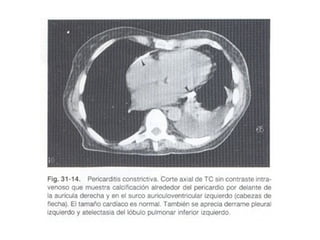

Las  calcificaciones pericárdicas resultan de la organización de exudado o sangre en saco pericárdico, que puede estar asociada o no con pericarditis constrictiva. La pericarditis constrictiva es más frecuente en tuberculosis. Sin embargo, pueden verse placas calcificadas pericárdicas en el 5 % de los pacientes con enfermedad reumática crónica. La calcificación es más densa en la zona de los surcos interventriculares y auriculoventriculares.

PERICARDITIS CONSTRICTIVA